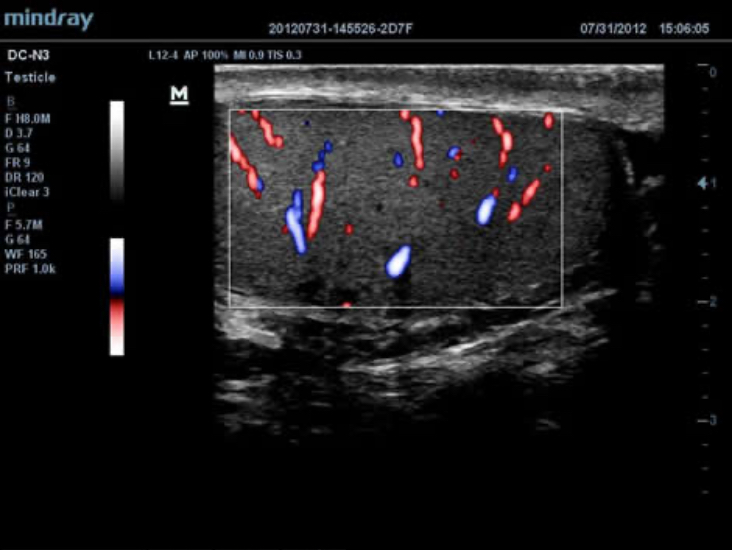

El DC-N3 PRO es la respuesta a sus requisitos de alta calidad de la imagen, versatilidad y asequibilidad. El DC-N3?PRO es el mejor equipo en su clase y es realmente una redefiniciĂłn de los principios bĂĄsicos que le brinda mucho mĂĄs que tan solo un sistema ecogrĂĄfico normal. Con caracterĂsticas avanzadas y el precio mĂĄs competitivo de la industria, se trata de ayudarlo a elevar sus expectativas.

El DC-N3 PRO es un sistema Doppler a color con todas las funciones que satisface sus necesidades de diagnĂłsticos mĂĄs rĂĄpidos, confiables y precisos. Gracias al mejor rendimiento, eficacia y dise?o de su clase, puede estar seguro de que obtendrĂĄ una experiencia de ecografĂa excepcional. Con su dise?o compacto, fĂĄcil de usar y ergonĂłmico, se puede mover, usar y ubicar segĂșn sus requisitos sin lĂmites.